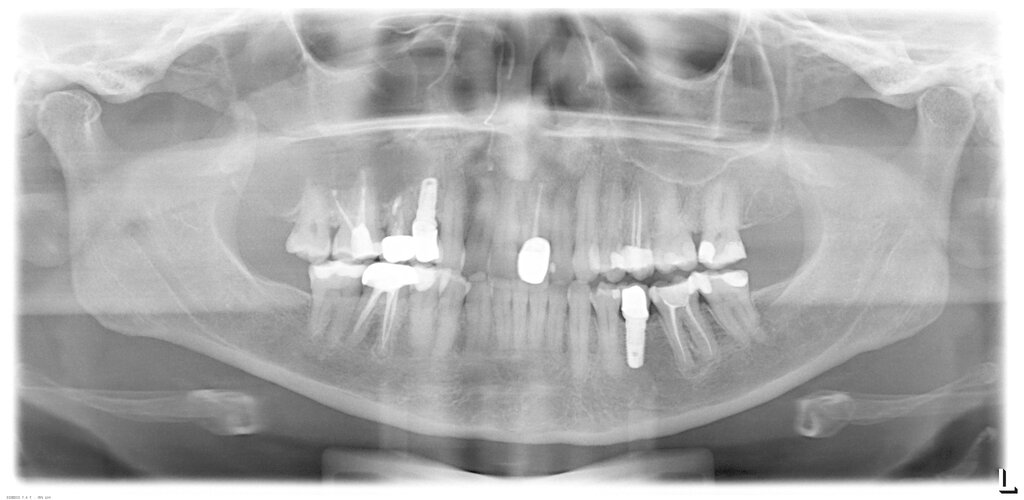

Neben der Frage nach der Chance des Zahnerhalts stellen Patienten häufig die Frage, ob sie durch die WSR Nachteile zu erwarten hätten, wenn sie sich später, bei Fehlschlag der WSR für ein Implantat entscheiden würden (Abbildung 6).

Tatsächlich ist die Datenlage zu dieser Fragestellung sehr dünn. Die Schwierigkeit der wissenschaftlichen Aufarbeitung und damit auch das Fehlen von Publikationen liegt in der Notwendigkeit einer sehr hohen Fallzahl sowohl bei der WSR und als auch bei der Implantattherapie, um Fälle zu finden, wo nach zunächst durchgeführter und später gescheiterter WSR der Patient dann an dieser Stelle tatsächlich ein Implantat bekommen hat und anschließend noch eine akzeptable Zeit in der Nachbeobachtung war. So war bei einer Studie von Saleh et al. [2021] das Screening von 1.241 Wurzelspitzenresektionen und über 9.000 Implantaten in einem 15-Jahres-Zeitraum notwendig, um am Ende 25 Studienteilnehmer für eine retrospektive Untersuchung einschließen zu können.

Hierzu wurde ein Datensatz mit 816 Implantaten bei 598 Patienten mit verfügbaren Röntgenbildern der extrahierten und ersetzten Zähne ausgewertet. Die Behandlungsfälle wurden in eine Gruppe mit (Gruppe A) und eine Kontrollgruppe ohne vorangegangene Wurzelspitzenresektion (Gruppe B) eingeteilt. Ein möglicher Zusammenhang zwischen der vorangegangenen Wurzelspitzenresektion und der Notwendigkeit einer späteren hartgeweblichen Augmentation mittels Schalentechnik beziehungsweise der klassischen Blockaugmentation wurde statistisch untersucht.

Insgesamt 437 Implantate (Gruppe A: 42, Gruppe B: 395) bei 309 Patienten, die am Nachsorgeprogramm teilnahmen, wurden darüber hinaus im Hinblick auf das Implantatüberleben und den periimplantären Knochenverlust ausgewertet. Die Fünf-Jahres-Implantatüberlebensrate wurde mit dem Kaplan-Meier-Schätzer berechnet. Der periimplantäre Knochenverlust wurde auf Röntgenbildern bis zu fünf Jahre nach Implantatinsertion vermessen.

Bei 11,5 Prozent des Gesamtkollektivs (94 Fälle) war eine Wurzelspitzenresektion durchgeführt worden. In 19,1 Prozent der Fälle der Gruppe A (mit vorangegangener WSR) und 26,6 Prozent der Fälle der Gruppe B (ohne WSR) wurde im Rahmen der anschließenden Implantattherapie eine hartgewebliche Augmentation durchgeführt: Der Unterschied war nicht signifikant (p = 0,12). Auch bei der der Fünf-Jahres-Implantatüberlebensrate (Gruppe A: 96,6 Prozent; Gruppe B: 98,0 Prozent) und dem marginalen periimplantären Knochenverlust wurden während des Fünf-Jahres-Follow-ups zu keinem Zeitpunkt signifikante Unterschiede zwischen beiden Gruppen berechnet [Kreisler et al., 2022].

Abgeschlossene apikale Defekte heilen nach Extraktion in der Regel problemlos aus und spielen daher für die spätere Implantattherapie keine Rolle. Problematisch sind Defekte, die bedingt durch eine ausgedehnte apikale Osteolyse keine oder fast keine vestibuläre Lamelle aufweisen (Abbildung 7), wobei dieses Problem bei einer Extraktion als Differenzialtherapie unverändert bleibt. Darüber hinaus können Fälle mit einer sekundär (nach der WSR) aufgetretenen Längsfraktur bekanntermaßen zu ungünstigen Knochendefekten führen.

Die Daten zeigen, dass eine vorangehende WSR die mögliche spätere Implantattherapie nicht negativ beeinflusst. Dies trifft sowohl für den Behandlungsaufwand als auch für die Implantatprognose zu. Es ist aus unserer Sicht wichtig, dies in jedem Aufklärungsgespräch auch so zu kommunizieren.